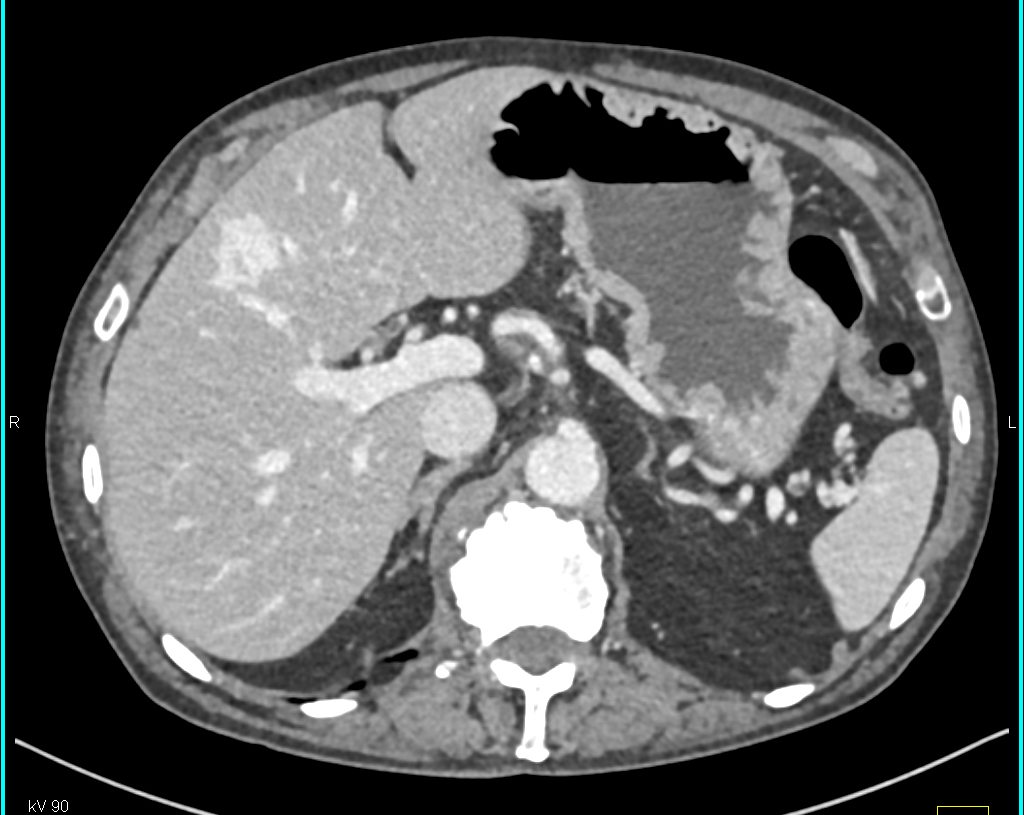

The best diagnosis in this case is?

metastatic PNET tumor

carcinoid tumor

hemangioma

hepatoma